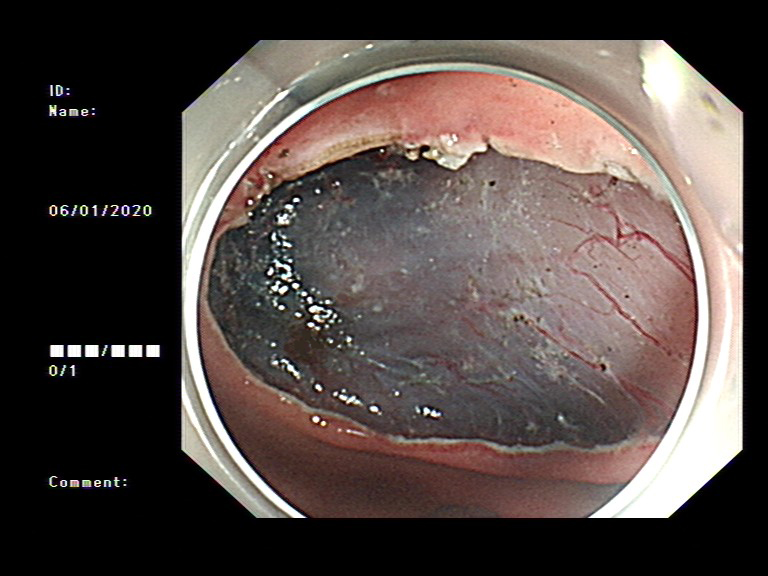

2020年1月,元旦刚过,大家都还沉浸在新年的喜悦中,来自隆安县的张阿姨一家却一筹莫展,张阿姨今年55岁,半年前开始出现上腹部胀痛不适,在当地医院一直按“慢性胃炎”服用中药及西药治疗,症状时好时坏。为了进一步治疗,来到我院就诊,内镜中心袁海锋主任亲自为其进行了无痛胃镜检查,经认真仔细观察发现胃内一处凹陷型病变,进一步行精细胃镜检查后,初步判断为早期胃癌病灶,而且病变侵犯深度局限在粘膜层内。经过与张阿姨及家属详细沟通后,决定用内镜下微创手术为其治疗。在内镜下确定病变边界后,顺利行内镜下粘膜剥离术(ESD)将病变完整切除。术后标本病理提示:早期胃癌(中分化管状腺癌)。治疗后一周,恢复良好,顺利出院,至今随访未诉明显不适。对于张阿姨一家来说,得了胃癌很不幸,但不幸中的万幸,她的胃癌被我们早期及时发现并完成了内镜下切除,避免进展为中晚期胃癌,使原本不富裕的家庭再雪上加霜。

图1 胃镜下早癌病灶

图2 ESD术及术后标本